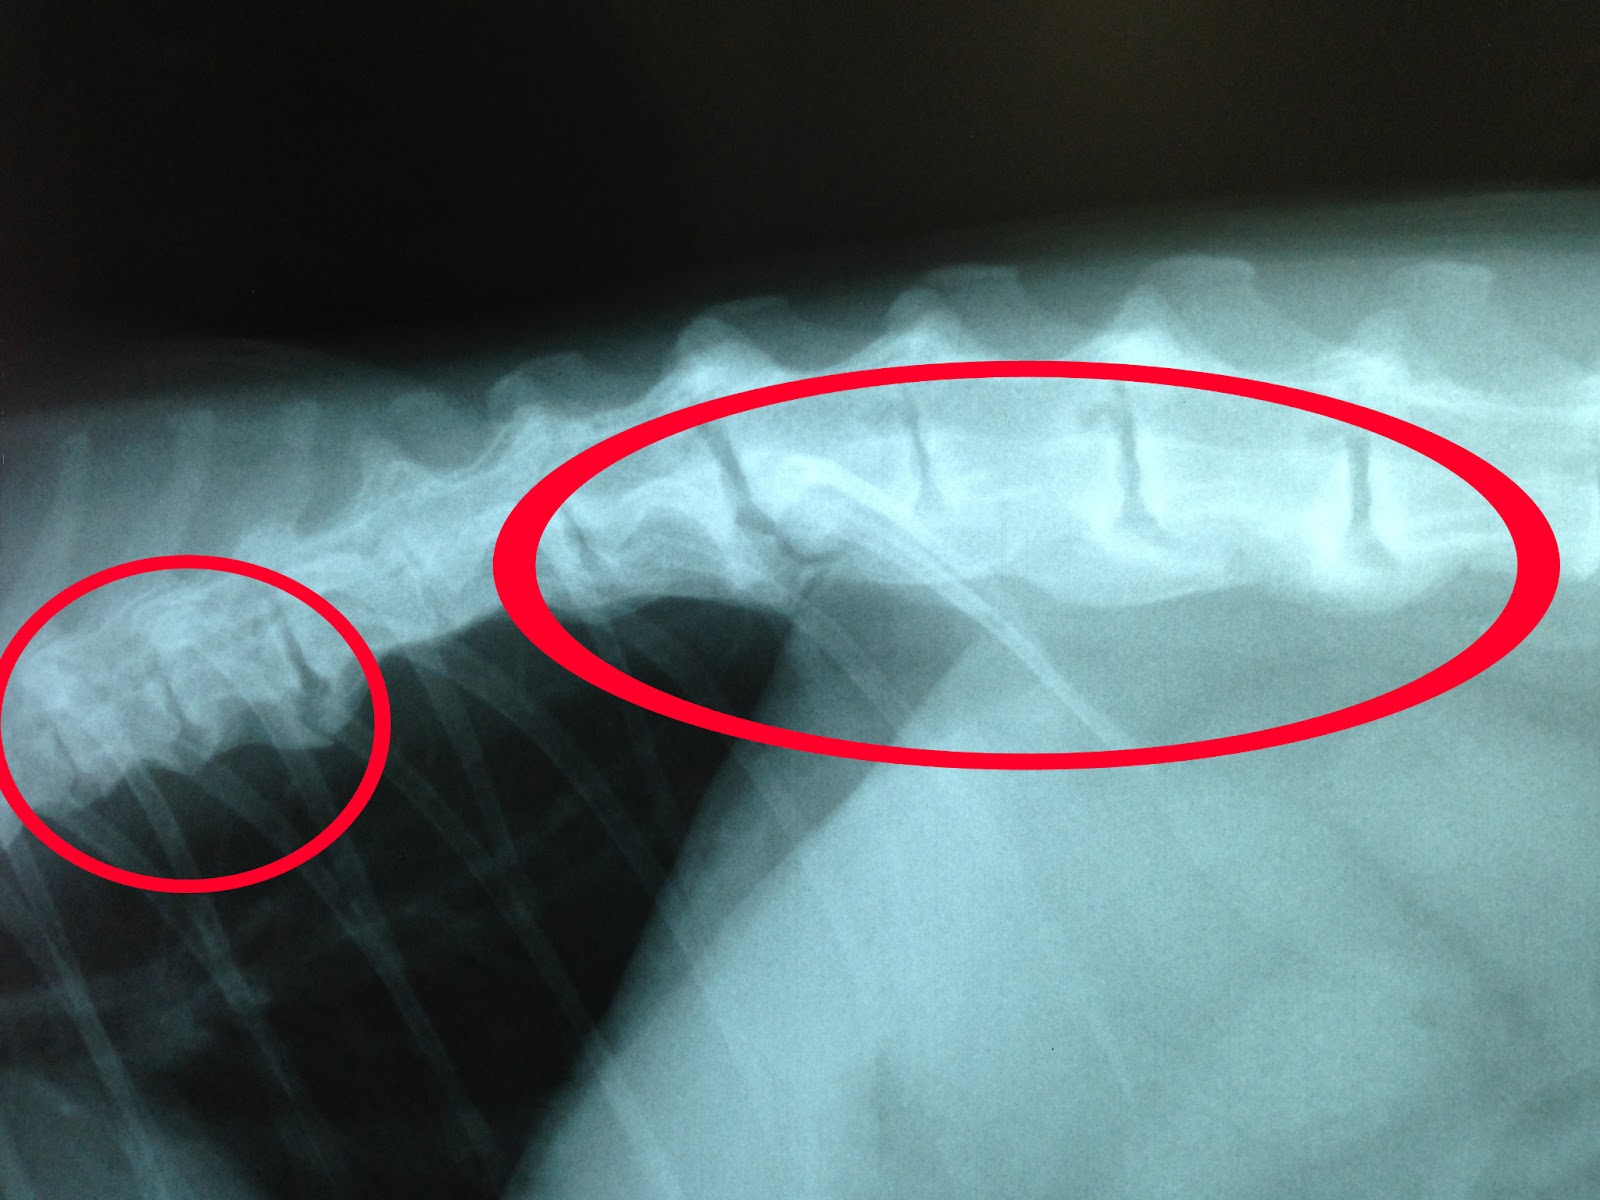

From todaysveterinarynurse.com

Discospondylitis in Dogs and Cats Signalment, Diagnosis, and Treatment Cat With Arthritis In Spine In one study, 90% of cats over the age of 12 had. And while the root cause of osteoarthritis in cats isn't. Over time there is a. yes, cats do get arthritis. a second study reported that 90% of cats older than 12 years of age had radiographic evidence of osteoarthritis, even though only 4% of these had. Cat With Arthritis In Spine.

From www.rygg.center

Spinal diseases Cat With Arthritis In Spine 2 in both studies, osteoarthritis was most prevalent in the shoulders, elbows, spine, coxofemoral joints, and tarsi. Over time there is a. It is an especially common health condition in senior cats. the disease most commonly affects the spine, hip, knee, ankle, and elbow joints in cats. In one study, 90% of cats over the age of 12 had.. Cat With Arthritis In Spine.